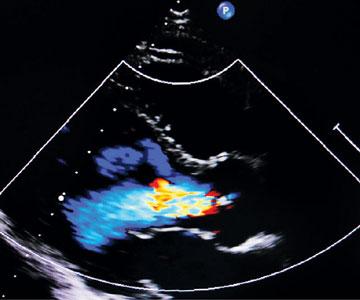

Seeing the Heart's Power

Robert Frederick

Biology

Medicine

Technology

Anatomy

Sightings